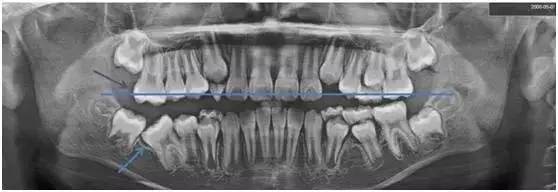

此时我才发现,她右侧下颌的“六龄齿”没有长出来,而其他三颗早已正常萌出了……这个情况引起了我的注意,我提议给她拍张X光片。

一看!果然右下“六龄齿”阻生(如图蓝色箭头处),我们向家长提出建议,必须进行早期治疗。

了解了“六龄齿”重要性之后,我们再回头看看小姑娘的X光片。

从X光片可以看到,小姑娘右下阻生的“六龄齿”,它的对合牙没有咬合接触,已经开始伸长。(以蓝色线为对标,紫色箭头指向的右上对合“六龄齿”较长)

再不处理,会占据右下阻生“六龄齿”的萌出空间,将来矫正难度将明显增大。